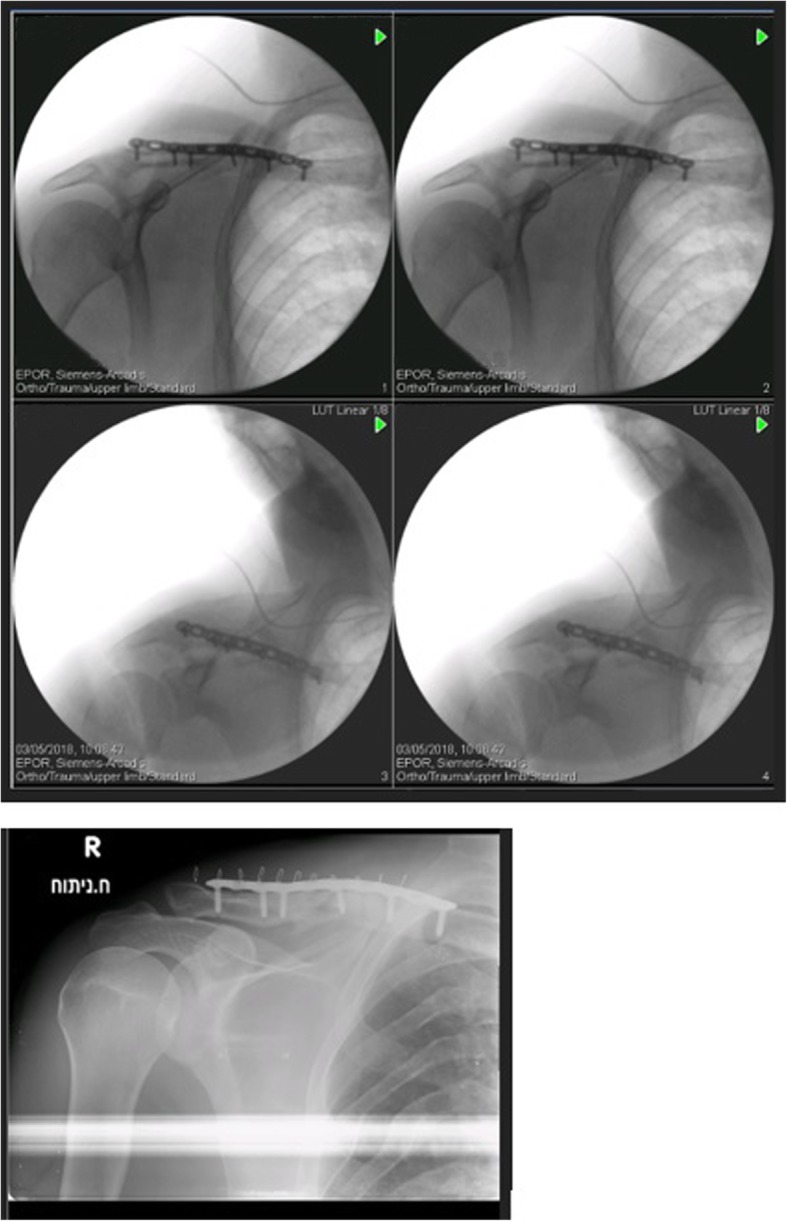

Fig. 4.

Second operation – intraoperative and postoperative imaging